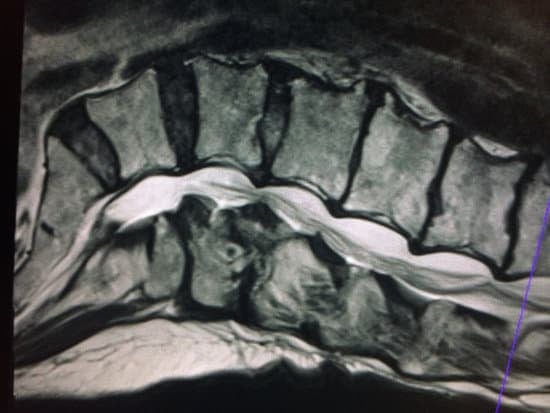

척추에는 척수 신경이 지나가는 통로(척추관)가 있습니다.

이 통로가 좁아지면서 신경을 압박하게 되는 질환이 바로 척추관 협착증입니다.

4. 진단 방법